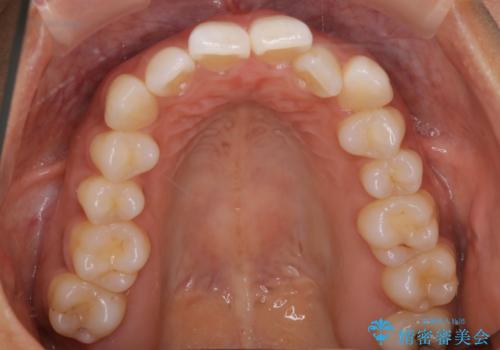

【インビザライン】前歯をきれいな歯並びにしたい

- 前歯の叢生を主訴に来院されました。このケースは抜歯をせずにIPRにてスペースを確保し、並べる計画をたてました。

きちんと使用時間を守って使用していただいたことで短い期間で治療が終了しました。